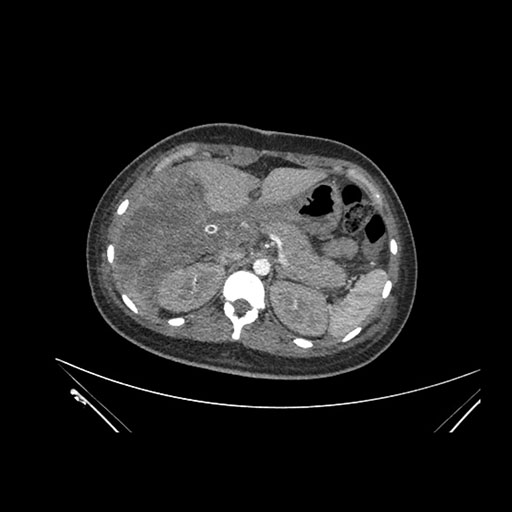

Imaging Analysis

Look through the patient's CT scan to identify any areas of concern for the necessary procedure.

Axial Arterial

Based on initial findings, which issue(s) would you be most concerned about?